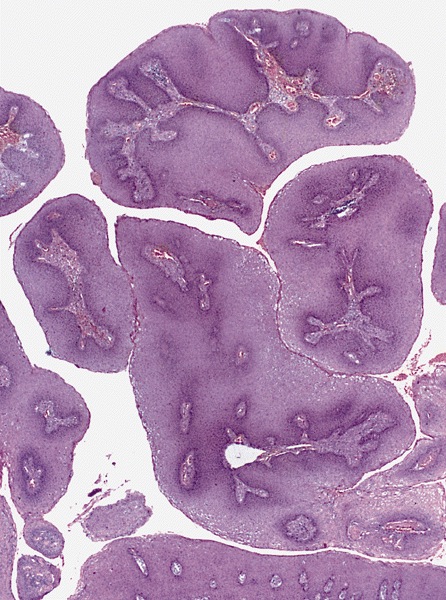

Microscopic (histologic) description

- Condyloma acuminatum (venereal / genital warts) (Head Neck Pathol 2019;13:80):

- More massive acanthosis with bulbous rete ridges (condyloma means fist or knuckle)

- Koilocytes in the upper spinous layer

- Parakeratosis ofen in the valleys of the epithelium (crypt parakeratosis) (see condyloma)

Microscopic (histologic) images

Contributed by Heba Ahmed Abdelkader, M.D., Hillary Rose Elwood, M.D., AFIP,

@MirunaPopescu13 on Twitter and @shilpa_rakesh_path on Instagram